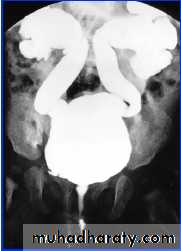

* Cystogram

VCUG/RNC

Reflux Seen on Voiding Cystourethrogram (VCUG) using transurethral contrast